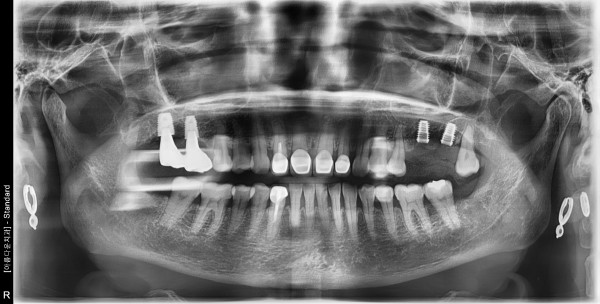

60세 여/ 상악 좌측 어금니 발치 및 치조골이식술 후 임플란트 식립